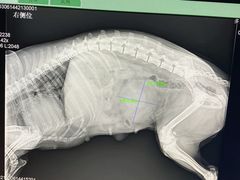

• 佑安动物医院·全科·内窥镜中心(幸福巷店)

• -佑安动物医院·全科·内窥镜中心(幸福巷店)

火山啊 | 21-09-26